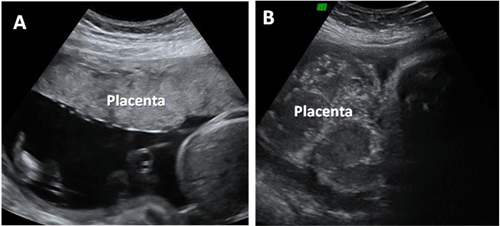

Las partículas se encontraron en las placentas de cuatro mujeres sanas que tuvieron embarazos y partos normales. Se detectaron microplásticos tanto en la parte fetal como materna de la placenta y en la membrana dentro de la cual se desarrolla el feto.

Se encontraron una docena de partículas de plástico. Sin embargo, solo se analizó alrededor del 4% de cada placenta, lo que sugiere que la cantidad total de microplásticos era mucho mayor. Todas las partículas analizadas eran plásticos que habían sido teñidos de azul, rojo, naranja o rosa y pueden provenir originalmente de envases, pinturas o cosméticos y productos de cuidado personal.

Los microplásticos tenían en su mayoría un tamaño de 10 micras (0,01 mm), lo que significa que son lo suficientemente pequeños como para ser transportados por el torrente sanguíneo. Es posible que las partículas hayan entrado en los cuerpos de los bebés, pero los investigadores no pudieron evaluar este aspecto.

En el estudio, publicado en la revista Environment International, los investigadores concluyeron: “Debido al papel crucial de la placenta en el apoyo al desarrollo del feto y en actuar como una interfaz con el entorno externo, la presencia de partículas plásticas potencialmente dañinas es una cuestión de gran preocupación. Es necesario realizar más estudios para evaluar si la presencia de microplásticos puede desencadenar respuestas inmunes o puede conducir a la liberación de contaminantes tóxicos, resultando en daños para los bebes a lo largo de su vida ”.